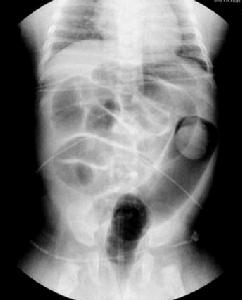

鋇灌腸是一種很老、也很成熟的檢查方法,它是通過將稀薄的鋇劑灌腸,以鋇劑來襯托出腸黏膜的形態改變片診斷疾病的,通過多張照片與正常腸黏膜進行對比分析得出診斷結果。鋇灌腸也可用於小兒的腸套疊復位。鋇灌腸檢查僅能看到消化道的輪廓,而且充滿鋇劑的消化道造影常掩蓋了微小的病灶,因此常口服發泡劑或向腸道注氣,使胃腸道內既有高密度的鋇劑,又有低密度的氣影,形成氣鋇對比造影,容易獲得陽性結果。用於消化道檢查的鋇餐是藥用硫酸鋇,因為它不溶於水和脂質,所以不會被胃腸道黏膜吸收,因此對人基本無毒性。[1]。

鋇灌腸檢查主要是用來診斷結腸病變的一種方法,即從肛門插進一個肛管、灌入鋇劑再通過X線檢查,診斷結腸腫瘤、息肉、炎症、結核、腸梗阻等病變。鋇灌腸檢查前病人需做如下準備:

由一次性的直接雙重氣鋇造影代替了傳統方法的充盈像、黏膜像、繼而再灌氣造成雙對比影像的作法。其優點是節省時間、用鋇量明顯減少,提高了診斷準確率。具體步驟是:檢查前先配製好雙重造影用的硫酸鋇,濃度為60-80-100%重量/體積(W/V)為宜。灌鋇前先注射低張性藥物,迅速取頭低30o俯臥位,將硫酸鋇經肛管注入直腸、乙狀結腸、降結腸、脾曲,再改換體位(右側臥位)再注入氣體,使鋇劑直達升結腸。鋇劑總量約200-300ml,空氣總量約600-800ml,撤除肛管,讓患者翻轉1-2次,按不同體位分別攝取各段結腸,均能獲得良好的雙對比影像。